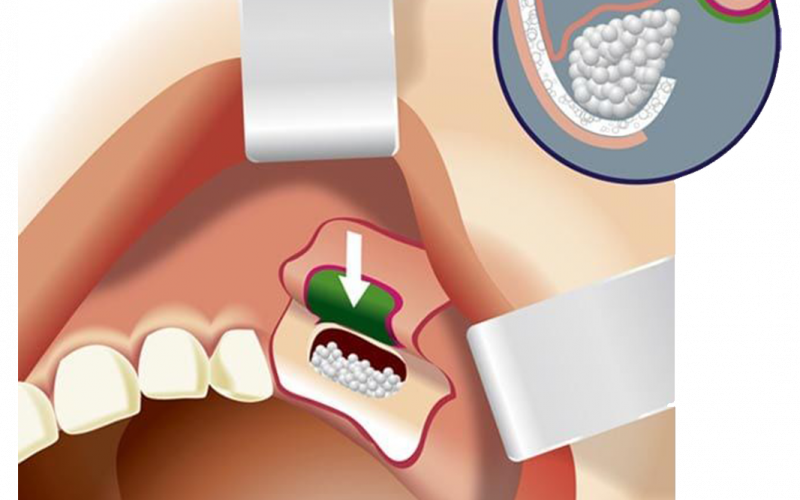

Lokal anestezi uygulandıktan sonra, diş hekimi veya çene cerrahı diş etinde kesi oluşturarak, sinüs membranını (zar) ortaya çıkarmak için çene kemiğinde bir “pencere” açılır. Daha sonra sinüs membranı uygun aletler ile eleve edilir yani yukarı kaldırılır.

Oluşan bu yeni boşluğa (çene kemiği ile sinüs zarı arasındaki boşluk) kemik materyali (kemik grefti) yerleştirilir ve kemik materyalini yerinde tutmak için üstüne genellikle bir kollajen membran yerleştirilir. Diş eti dokusu daha sonra dikişlerle kapatılır.